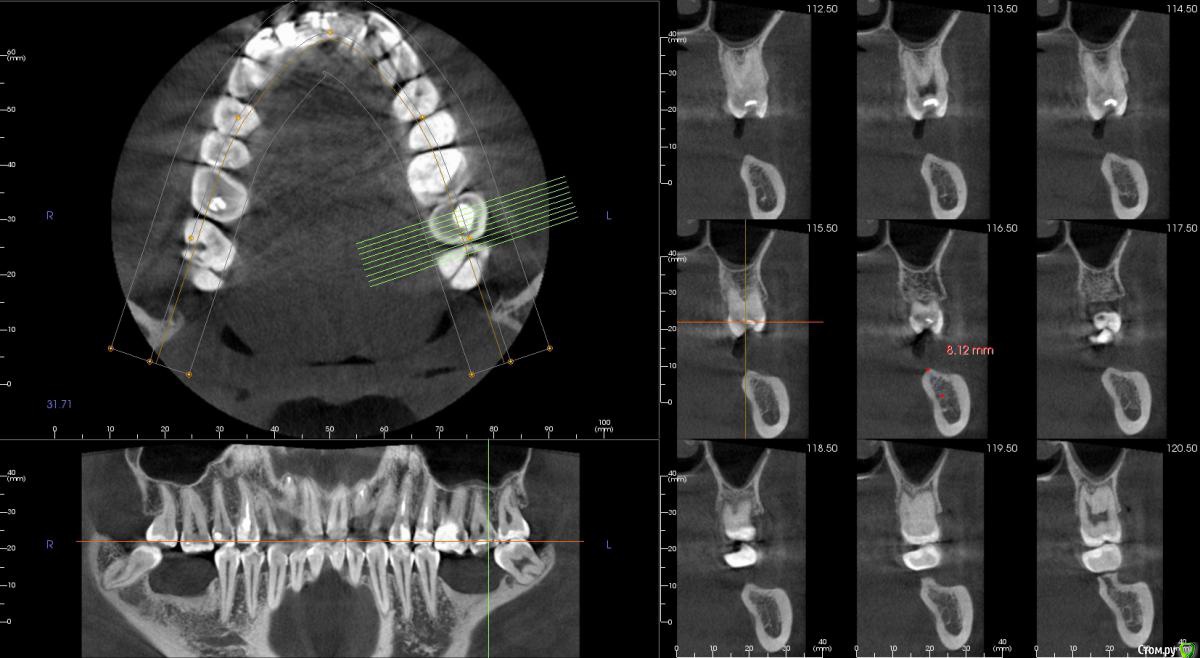

Господа как лучше тут поступить? поменьше бы рисков)

" всеводинэтап"крыша гаража" и латерализация отменяются)))

вижу вариант только с сеткой.

Из того что разобрал по срезам мне кажется можно медиально расщепить и притопить, дистально 4х6 поставить (астра, штрауманн...). Посмотрите, помещаются ли такие импланты. Травма меньше, быстрее и меньше рисков.

Сделайте нкр с медиальными болтами, дистальные глубже установите.

Тогда десну аля шашлычки и фдм отсроченно.

Далее временное протезирование.